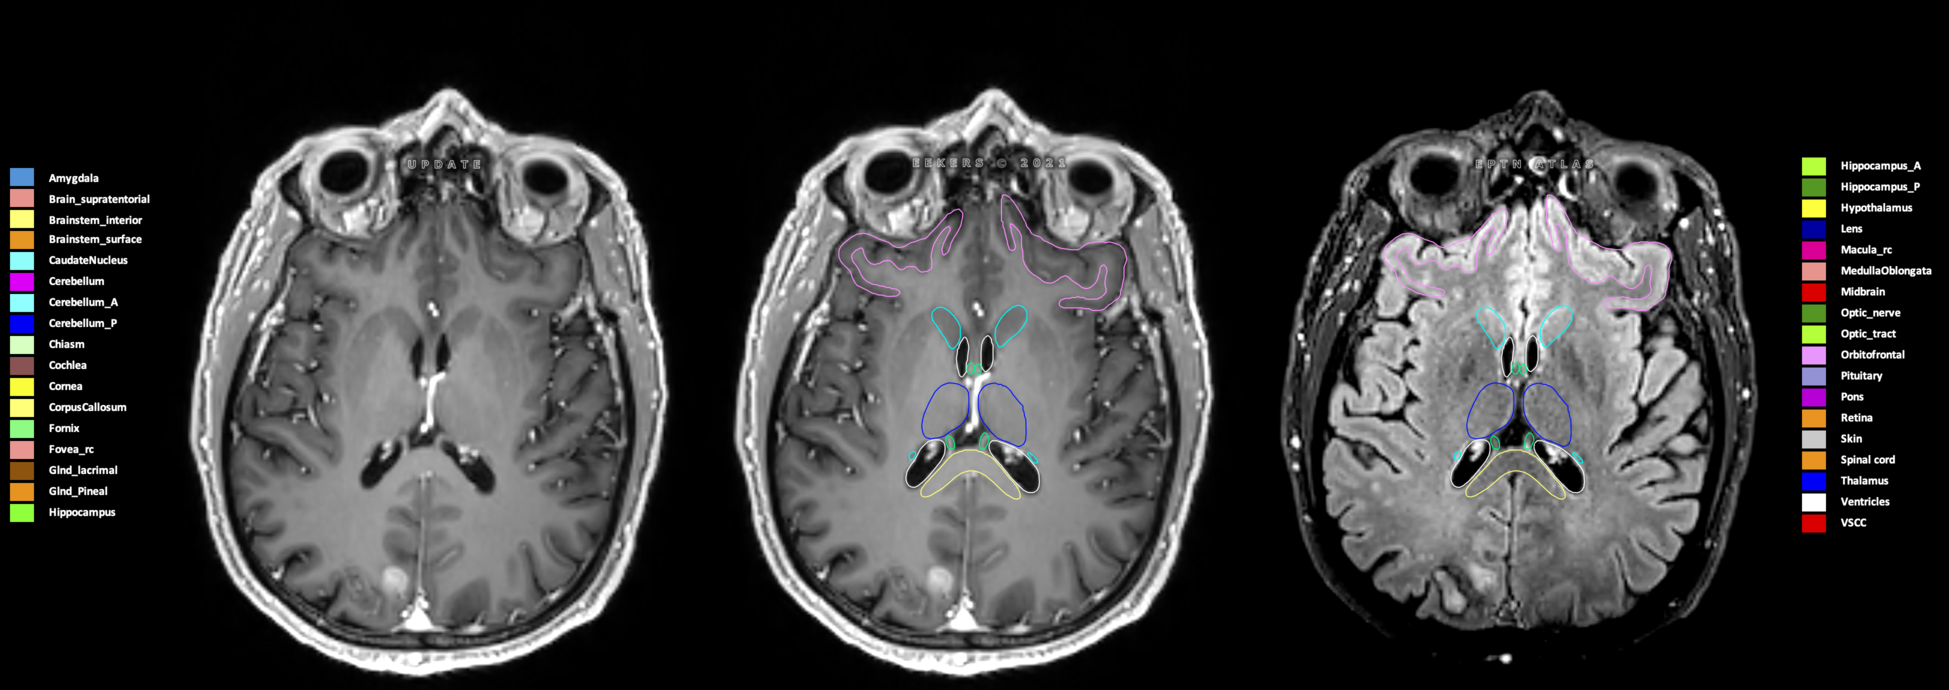

Eekers et al. have published an international neurological atlas for contouring of organs at risk in consensus with the European Particle Therapy Network (EPTN) in 2018 and an update in 2021. The purpose of this consensus atlas is to decrease inter- and intra-observer variability in delineating OARs relevant for neuro-oncology.

Included are all OARs known to be relevant for radiation-induced toxicity in neuro-oncology: brain, brainstem (midbrain, pons, medulla oblongata), chiasm, cerebellum (anterior & posterior), cochlea, cornea, hippocampus (anterior & posterior), hypothalamus, lens, lacrimal gland, optic nerve, pituitary, skin, and vestibular & semicircular canals. To further facilitate research on cognition, vision and radiological changes after irradiation of the brain, potential clinically-relevant OARs are included: amygdala, caudate nucleus, cerebellum (anterior & posterior), corpus callosum, fornix, macula, optic tract, orbitofrontal cortex, periventricular space (PVS), pineal gland, and thalamus.

Three-dimensional delineation of the 25 consensus OARs for neuro-oncology are shown on CT (WW/WL 120/40, 3000/600), 3T MR images, (T1Gd, T2FLAIR 1mm) and 7T MR (MP2RAGE 0.7 mm). All are presented in transversal, sagittal and coronal view.